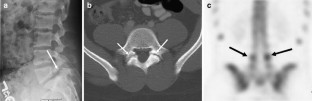

Fig. 3